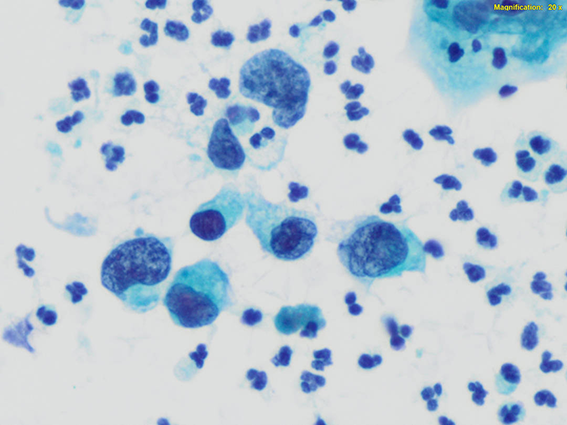

El Pap es una tinción

policromática

que permite un

detallado

estudio

de

la cromatina y

la

diferenciación

citoplasmática

(queratinización,

metaplasia,

etc.).